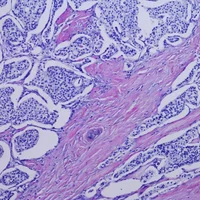

Cancers

Tumeurs malignes